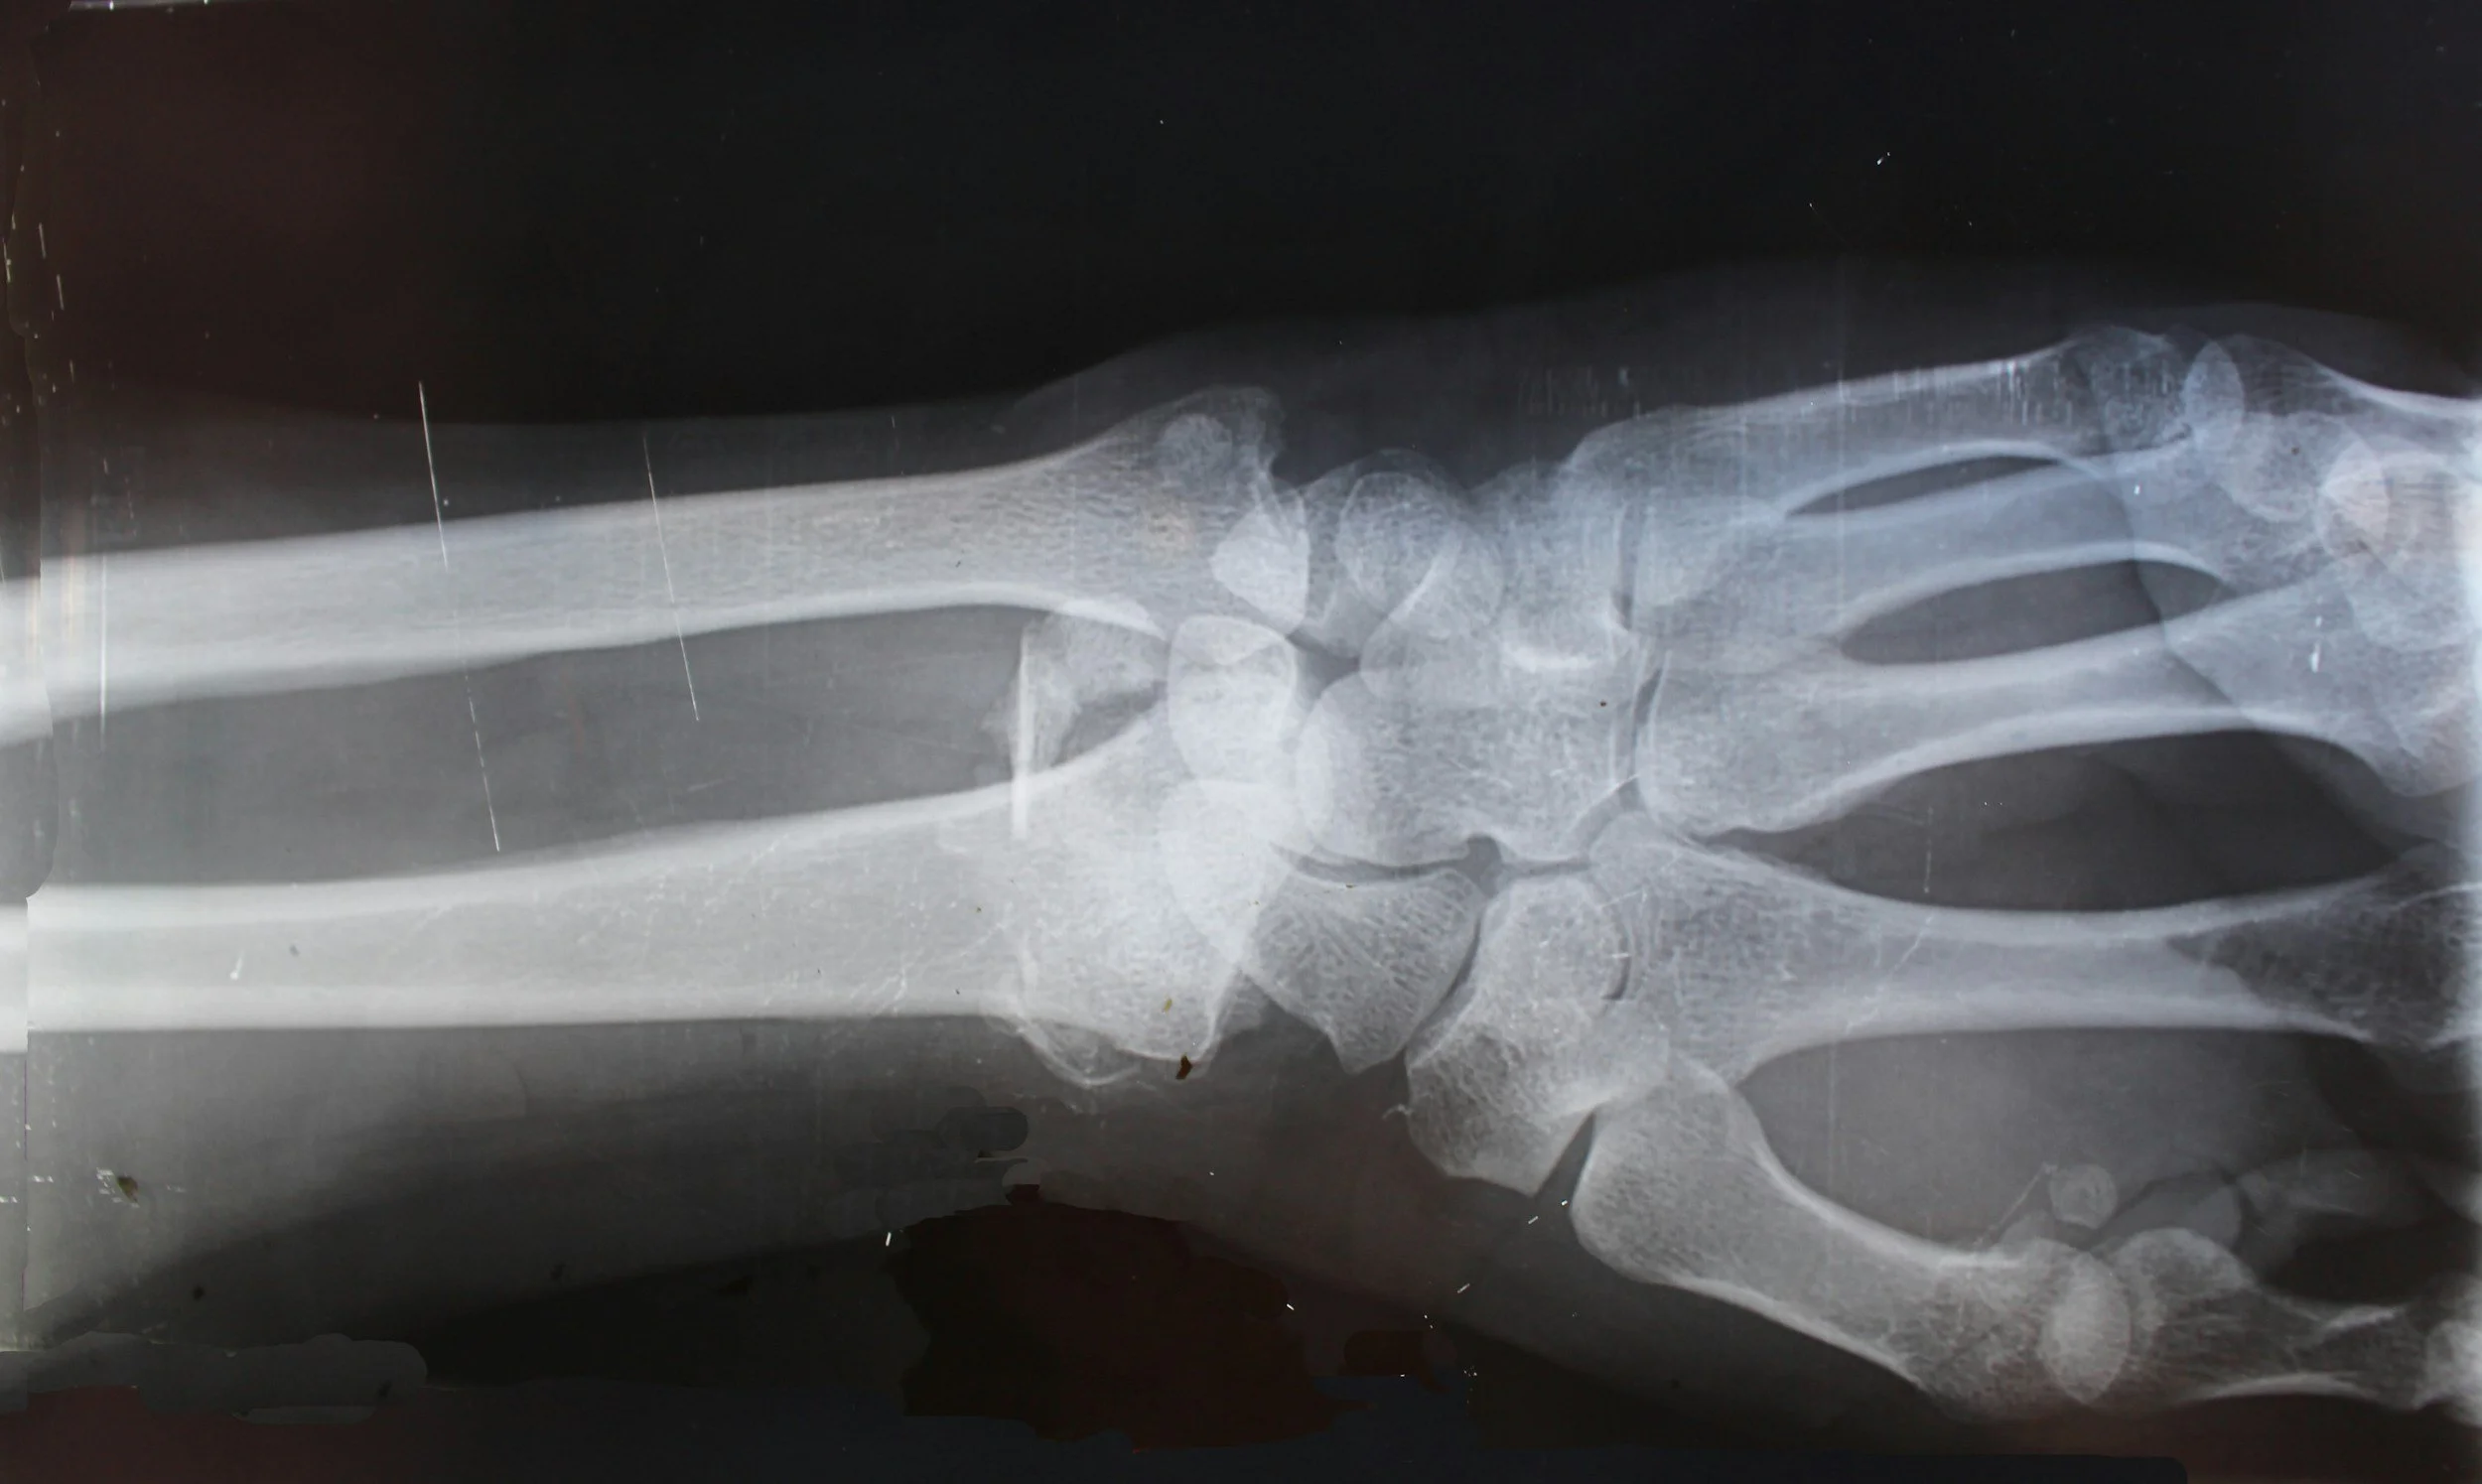

A pediatric x ray is a safe and common imaging test that allows doctors to view bones and certain internal areas. It can help identify fractures, joint problems, swallowed objects, or certain infections. Medical teams at Care+ use imaging when it is necessary to understand a child's condition.

Doctors may recommend a pediatric x ray when a child experiences an injury from sports, playground activity, or a fall. Pain in an arm, leg, wrist, or ankle can sometimes mean a fracture or sprain. Imaging helps doctors confirm the injury and decide the best treatment plan. Care+ provides evaluation for many common injuries that affect children.

A pediatric x ray can also help doctors understand certain illnesses. For example, imaging may be used to examine the chest if a child has breathing problems or symptoms of pneumonia. In other situations, it may help locate objects a child accidentally swallowed.